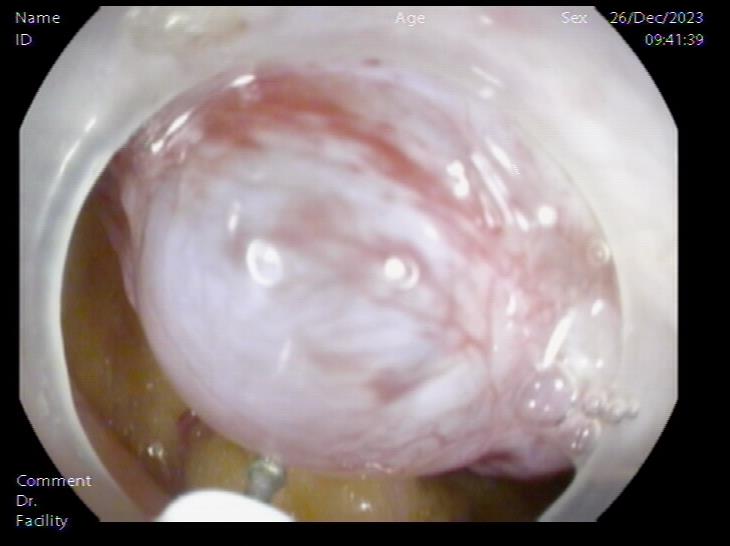

腹腔内囊肿 腹腔内囊肿近景

患者,66岁,女性,平素身体健康,以“发现胃肿物2年余”主诉入院,既往于外院行电子胃镜检查发现胃底隆起,直径约1.5-2.0cm,超声内镜检查考虑黏膜下来源间质瘤可能,不除外壁外病变压迫。外院CT提示胃底浆膜下囊性病变可能。患者及家属诊治心切,辗转数家医院后为求内镜下治疗遂来二附院。入院后在消化内科再次超声内镜检查,提示胃壁增生病变可能,增强CT提示胃底胃壁增厚,结合内镜检查。患者及家属强烈要求内镜下探查及病变切除术。术前在王进海主任的指导组织下,进行了专业组内及多学科讨论,与患者及家属充分沟通后,决定行内镜下切开探查及病变治疗术,必要时可行内镜-腹腔镜联合手术(LECS)。邹百仓教授带领内镜下肿瘤诊治及超级微创手术团队施行手术,术中逐层切开胃壁黏膜层及黏膜下层,暴露固有肌层,未发现胃壁病变,遂切开胃壁全层,局部腹腔探查,切口附近腹腔内似韧带组织上发现半球形隆起,表面透亮光滑,大小约1.5X1.5cm,术中请外科李军辉及袁庆攻教授会诊后确诊为囊性病变,讨论后建议可以观察或内镜切开引流,与患者家属沟通后家属强烈要求切开引流,遂用内镜切开刀切开囊肿,引流少量清亮囊液,囊肿塌瘪,观察囊肿切口及局部无出血,切除局部部分胃壁组织送检,内镜下严密关闭切口,留置胃管后,返回病房,常规对症治疗1周,患者无并发症发生,正常出院。